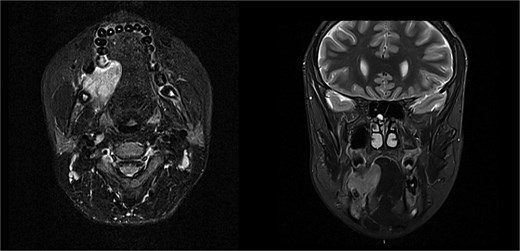

The patient was admitted from the clinic for urgent evaluation. Routine blood investigations were normal. An orthopantomogram revealed displacement of the second and third molars and a poorly defined superior margin of the alveolar process, suggesting osseous involvement (Fig. 2). Contrast-enhanced computed tomography (CT) of the facial bones and neck demonstrated a well-defined lucent lesion within the mandibular body with exophytic soft tissue extension into the oral cavity (Fig. 3). Magnetic resonance imaging (MRI) of the neck illustrated the hyperintense soft-tissue component with no rim enhancement or necrosis (Fig. 4). There was no lymphadenopathy noted clinically or radiograpgically.

Solid enhancing right osteolytic mandibular lesion with small necrotic components within it. Infection/abscess less likely due to absence of fat stranding/rim enhancement (MRI).